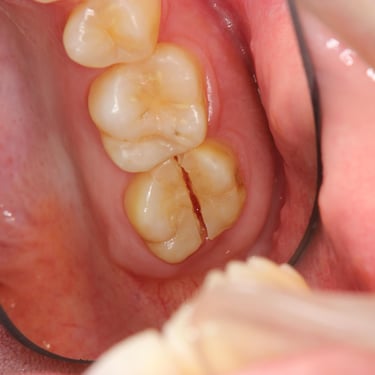

Fractura Radicular Vertical

Una fractura radicular vertical es una fisura que se extiende a lo largo de la raíz del diente, a menudo causada por un trauma o una presión excesiva.

Los pacientes suelen sentir dolor al morder y pueden notar hinchazón.

La fractura generalmente requiere la extracción del diente, ya que es difícil de reparar. Es crucial tratarla rápidamente para evitar infecciones.